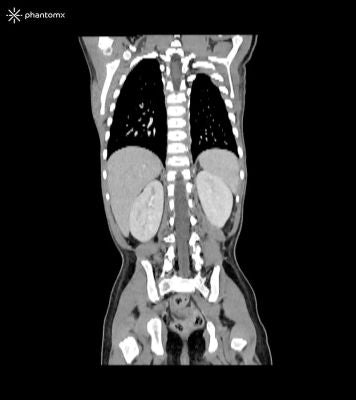

Description

This phantom simulates the contrast-enhanced thorax, abdomen and pelvis of a 3-year-old child in the portal venous phase. It covers the sixth cervical vertebra to the perineum.

The phantom can be used in CT (including CBCT) and X-ray imaging to evaluate and optimize imaging performance and post-processing applications, including AI-enabled applications. It is also suited for training purposes.

The phantom provides a detailed and realistic simulation of soft and bone tissue. Air voids including those of the lungs are filled with a cellulose-polymer composite of approx. -160 HU.